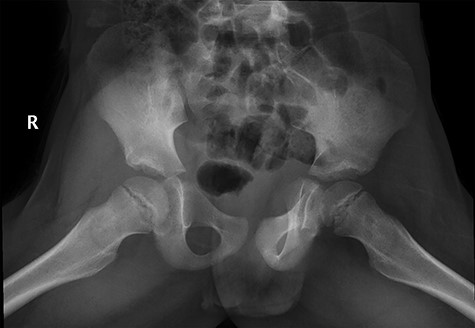

CT hips reported a well-defined lesion seen bilaterally in the neck of femur anterior infero-medial aspect, more prominent on the left side measuring 7 x 3 mm on left side both in coronal (Fig. 3) and axial (Fig. 4) views. On the right side, other lesion measuring 2 x 1 mm (Fig. 5) seen in coronal view. These two lesions are well defined with a sclerotic border with a small cortical defect. The lesion shows fat density. The symmetrical appearance of the lesion combined with the fat density and location suggest the diagnosis of synovial herniation pit. MRI Pelvis revealed minimal left hip joint effusion with loculated fluid seen along the trochanteric bursa with the largest measuring 0.9 x 1.5 cm (Fig. 6, 7).

Sowed coronal cut of CT hips demonstrating the synovial pit on left and right side.

Follow-up X-ray showed regression of the lesion in the form of progression of the dense sclerosis of the defect of the left femur while the right femur neck lesion is barely visible (Figure 10) and advised for watchful waiting.